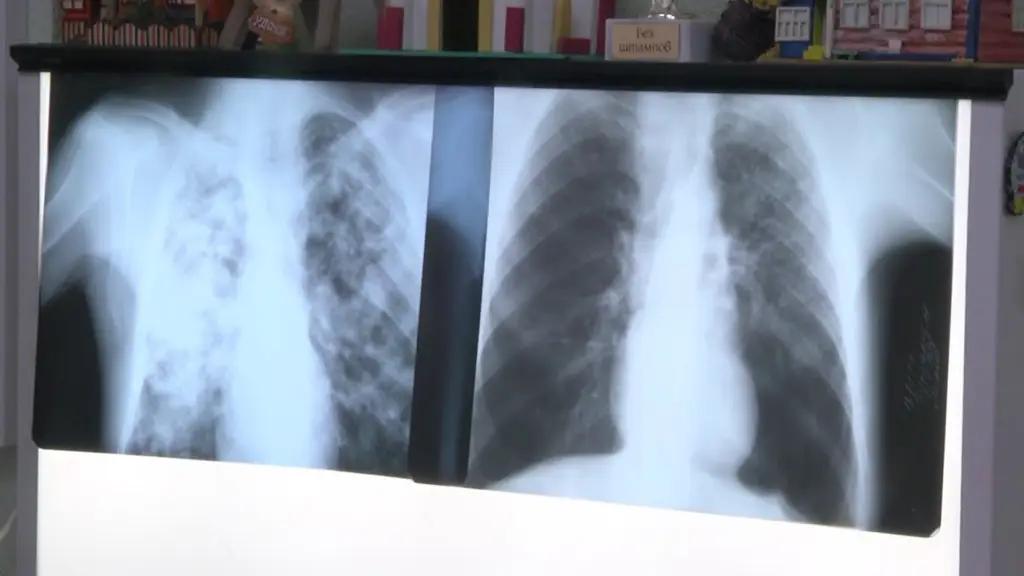

20.05.2022, 06:18Кабинет министров КР хочет направить 1.2 млрд сомов на борьбу с туберкулезом. Об этом сообщается в проекте постановления, который вынесен на общественное обсуждение.

Программа «Туберкулез-VI на 2022—2026 годы» определяет задачи госполитики Кыргызстана, направленные на стабилизацию ситуации по туберкулезу, в условиях деструктивного влияния пандемии коронавируса, а также постепенное улучшение эпидемиологической картины в стране. Программа определяет новые приоритеты в области контроля туберкулеза, восстановление последствий эпидемии COVID-19 на систему оказания противотуберкулезной помощи.

В справке-обосновании отмечено, что эпидемиологическая ситуация по туберкулезу в стране остается все еще тревожной. В 2018 году Кыргызстан принял обязательства по ликвидации эпидемии туберкулеза к 2030 году, а именно сокращение смертности от туберкулеза на 95%, снижение числа новых случаев заболевания туберкулеза на 90%, снижение финансового бремени на пациентов с туберкулезом.

«В 2020 году в Кыргызстане выявление случаев туберкулеза сократилось на 32% по сравнению с 2019 годом. Данный фактор наряду с высокой распространенностью МЛУ ТБ (30%) может резко ухудшить эпидемиологическую ситуацию с туберкулезом в стране в ближайшие несколько лет. Учитывая, что пандемия COVID-19 также усугубила уровень бедности, риск инфицирования и развития заболевания туберкулезом, последствия могут быть еще более грозными», — отмечает кабмин.